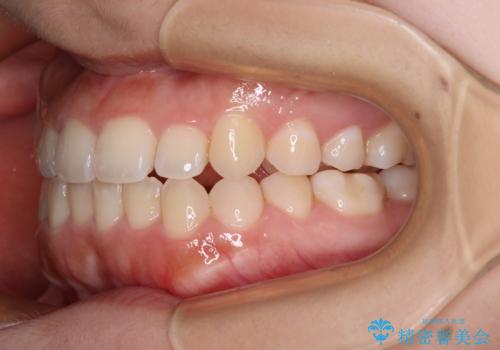

- 上下前歯のクロスバイトと叢生を気にして来院された患者様です。

インビザラインでの治療を希望されていて、デコボコの程度が中等度であり、安価なパッケージにて対応可能と判断されたため、インビザライン・モデレートを用いて矯正治療を行うこととしました。